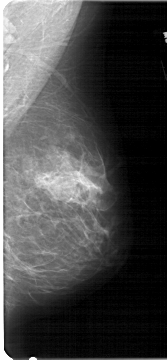

A_1268_1.RIGHT_MLO

RIGHT_MLO LINES 5386 PIXELS_PER_LINE 2491 BITS_PER_PIXEL 12 RESOLUTION 43.5 NON_OVERLAY